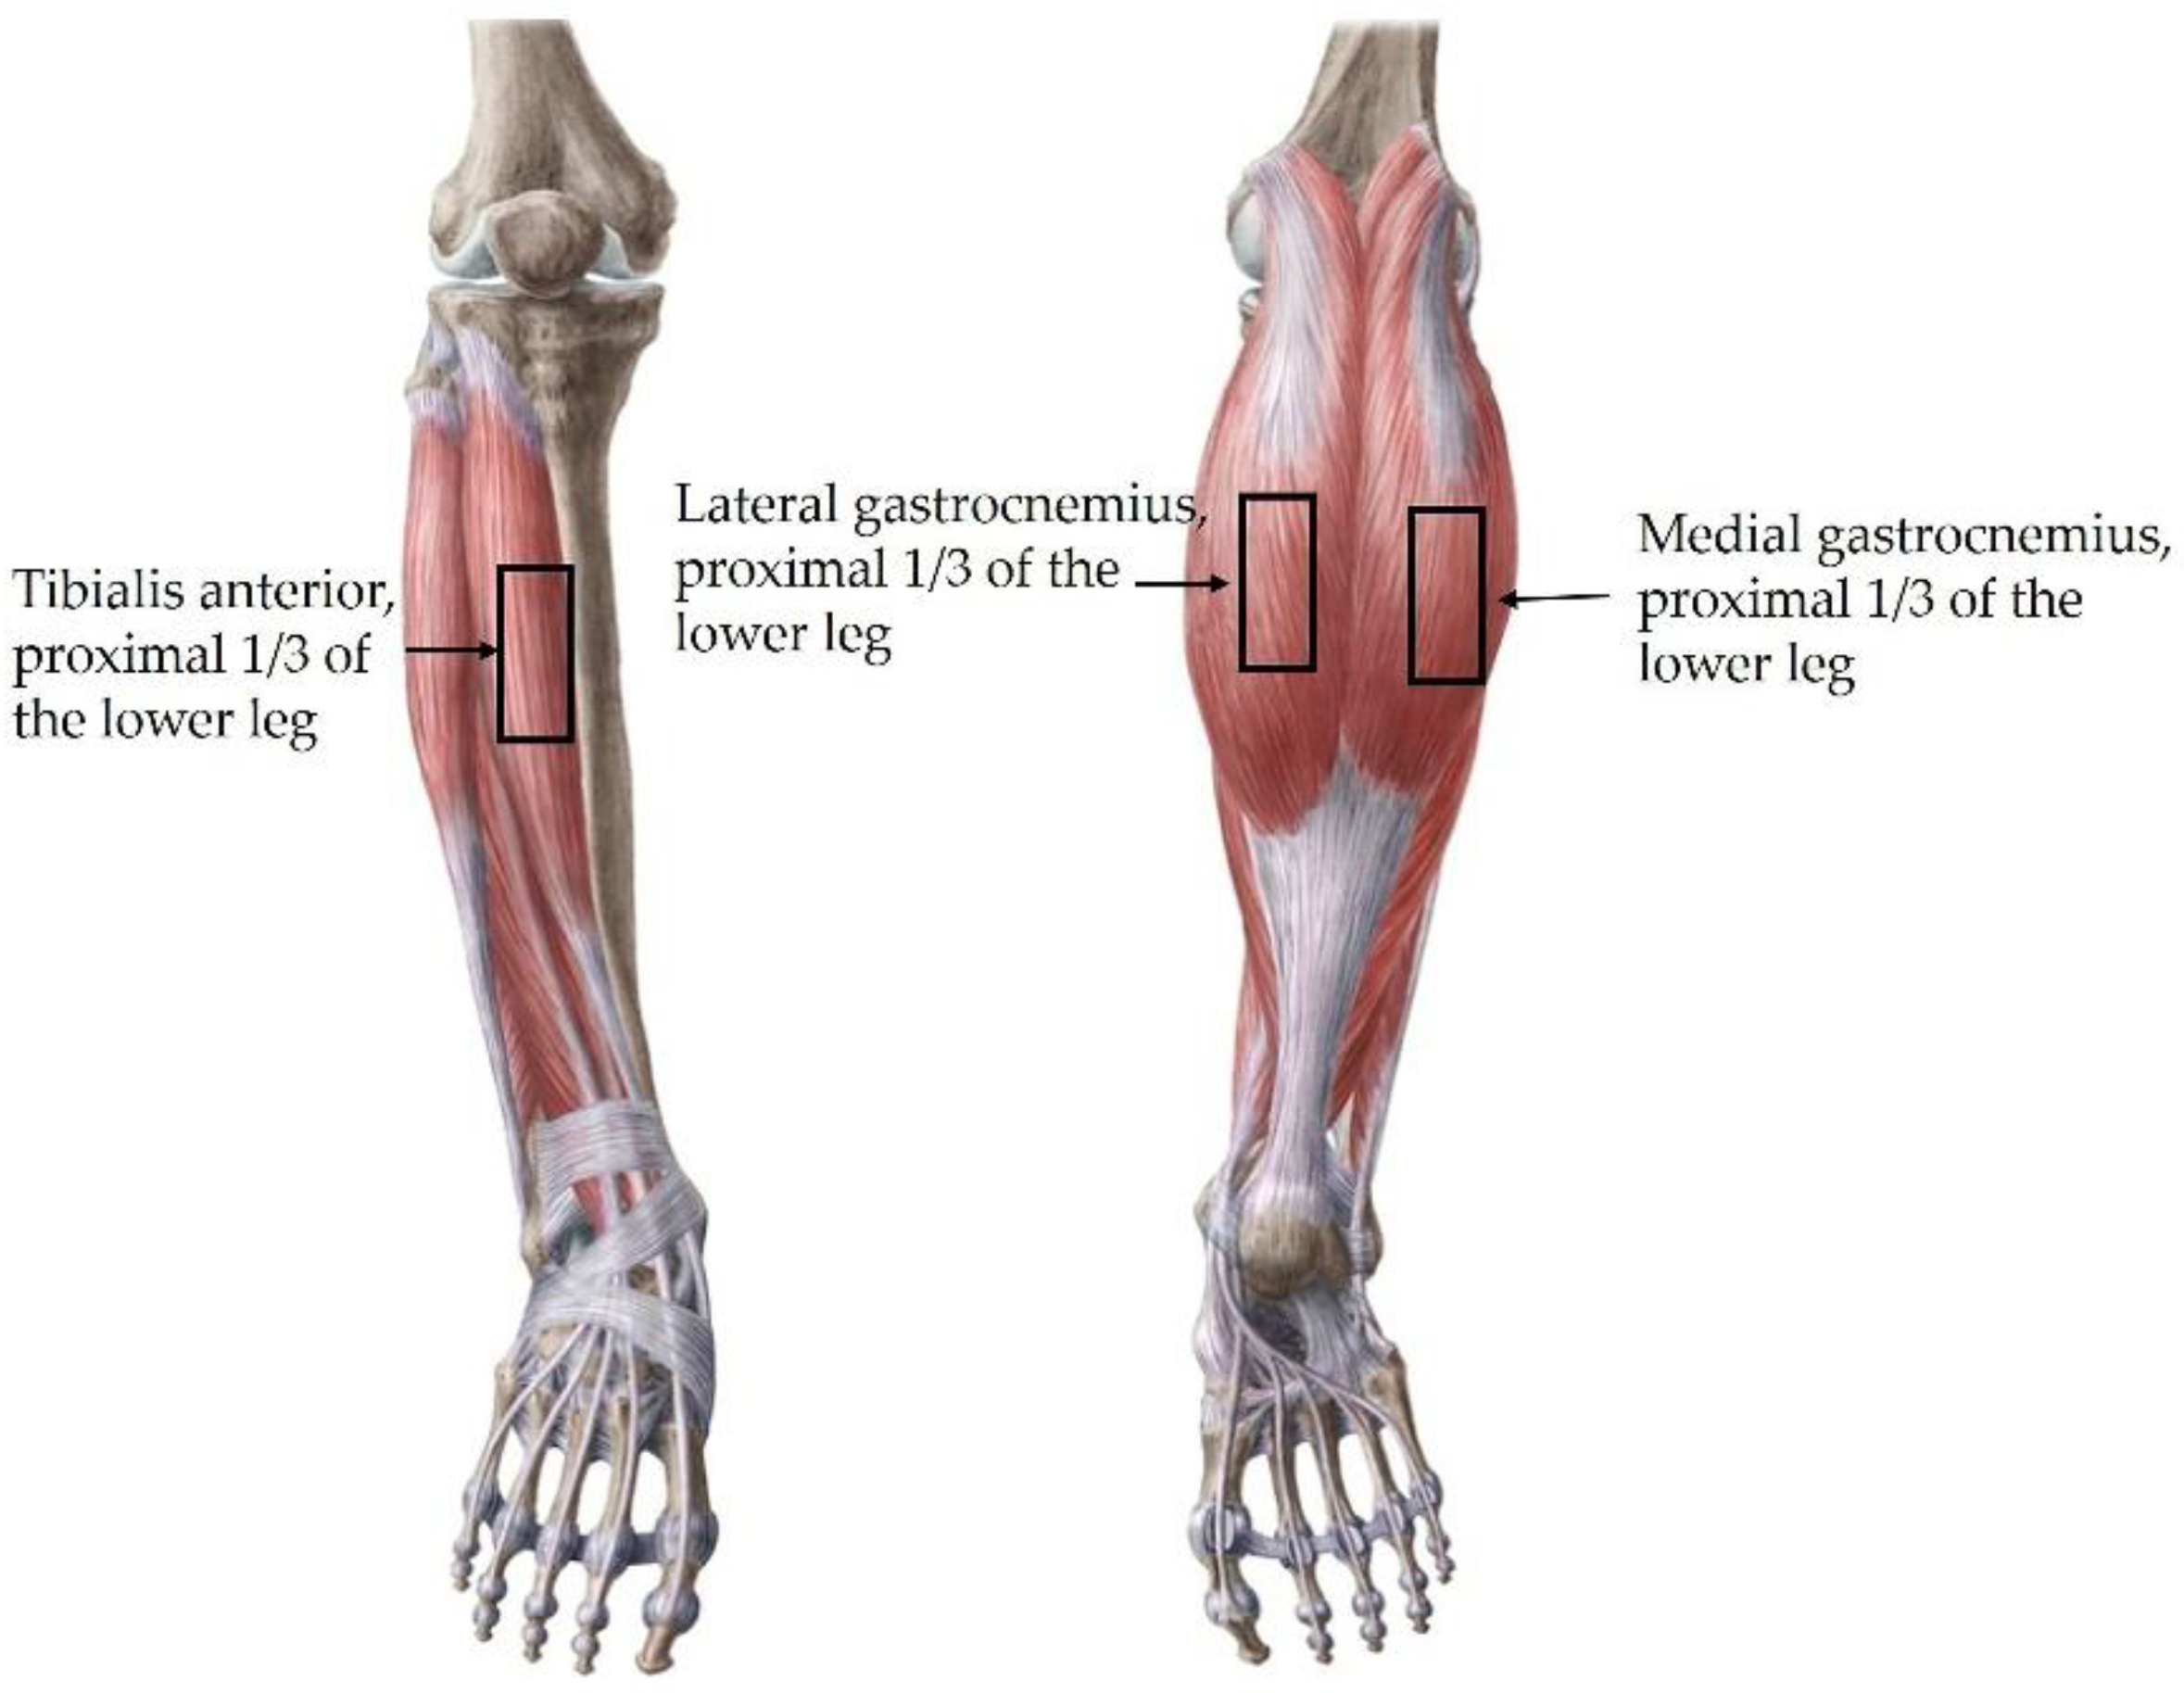

2.3.4. Stiffness and Thickness of the Muscle